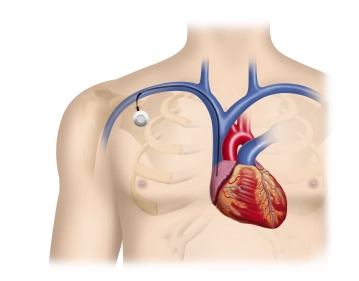

Final Functional Check

Soundsettings Before skin closure, perform a transcutaneous test puncture of the port reservoir and, if necessary, re-visualize the catheter system with contrast medium under fluoroscopy.

Postoperatively, along with the exclusion of a puncture pneumothorax, the radiological verification of the correct position of the port system is performed on a chest overview image.